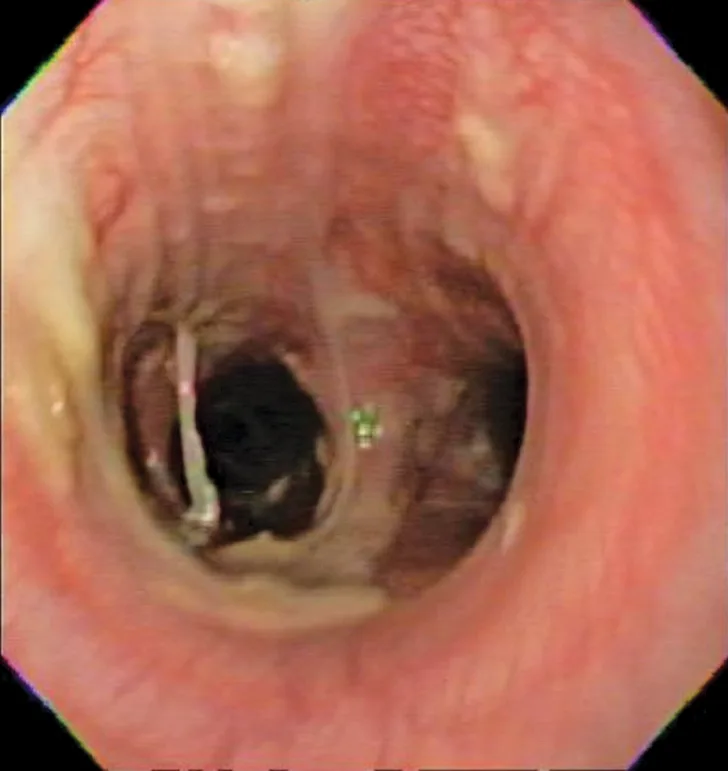

Bronchoscopic visualization revealed a moderate amount of thick, adherent, greenish-yellow mucus in the trachea and secondary and tertiary bronchi; mucosa was moderately irregular and erythematous (Figure 2). There was no evidence of airway collapse. Samples were collected via bronchoalveolar lavage for cytology, aerobic culture, and Mycoplasma spp culture.

Bronchoscopy results demonstrating mucosal irregularity, hyperemia, and characteristic greenish-yellow airway exudate

Cytologic evaluation of the airways confirms eosinophilic inflammation, which is the hallmark of diagnosis. The percentage of eosinophils (mean, 61% of the total nucleated cell population4) exceeds that of healthy dogs (5%-24%).2,5,10 Samples can be obtained via tracheal wash or bronchoscopy. Bronchoscopy allows for visualization of more characteristic airway associated changes (eg, greenish-yellow secretions, irregular mucosa, hyperemia).2,5,11 Occasionally, intraluminal granulomas may be present,4 allowing for mucosal brush samples or biopsies that can further support a diagnosis. Tracheal washes provide appropriate cytologic samples in most cases. Bronchoscopy is generally reserved for patients with more focal radiographic disease, concerns for neoplasia, or suspicion for concurrent structural disorders (eg, bronchial collapse, tracheal collapse).